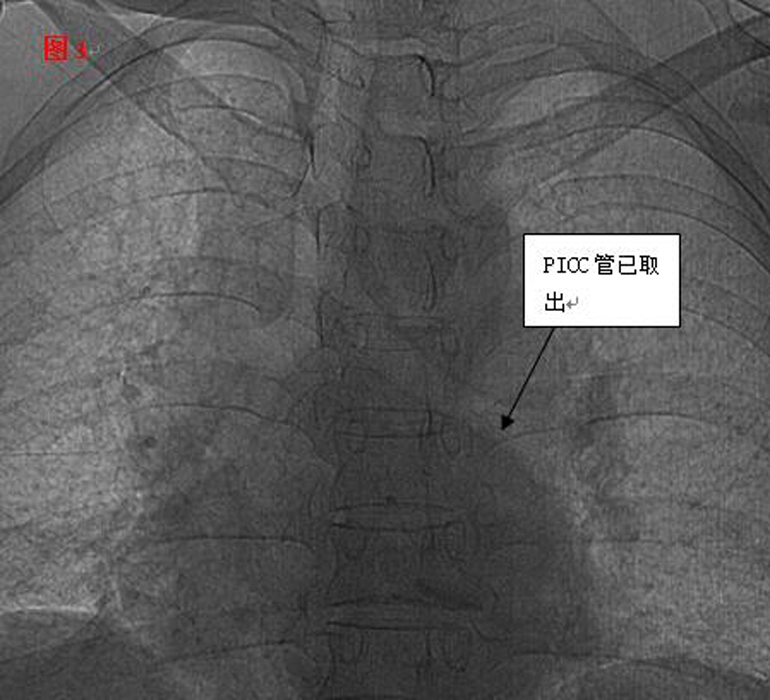

??? 手術(shù)遇到了艱巨的挑戰(zhàn),需更改手術(shù)方案。血管外科專(zhuān)家王李華教授及陸煒主任短暫商討后,臨時(shí)施妙招,先將PICC導(dǎo)管拉出心臟,再將圈套器牽引導(dǎo)管至下腔靜脈,捕捉后緩慢拉出體外,導(dǎo)管竟長(zhǎng)達(dá)30cm(見(jiàn)圖2)。

??? 憑借醫(yī)師的高超技術(shù)加上團(tuán)隊(duì)的密切合作,手術(shù)圓滿(mǎn)成功,30厘米的導(dǎo)管被完整取出,術(shù)后復(fù)查未見(jiàn)殘留。當(dāng)手術(shù)結(jié)束的那一刻,躺在手術(shù)臺(tái)上的麗琴由衷的感謝聲,以及在場(chǎng)觀(guān)摩學(xué)習(xí)人員的掌聲,讓手術(shù)室內(nèi)格外溫情。